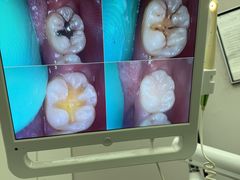

• 牙博士口腔品牌连锁(杨浦店)

• -牙博士口腔品牌连锁(杨浦店)